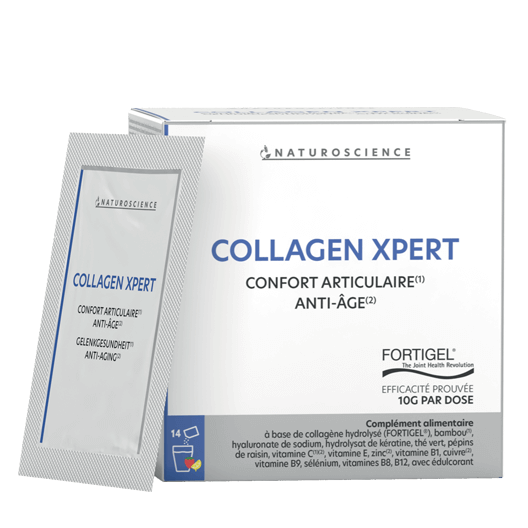

Pour prévenir les risques liés à une tension artérielle élevée, le Laboratoire NaturoScience a conçu un complément alimentaire à base de 3 plantes reconnues pour renforcer le système cardiovasculaire et favoriser le retour d’une tension normale.